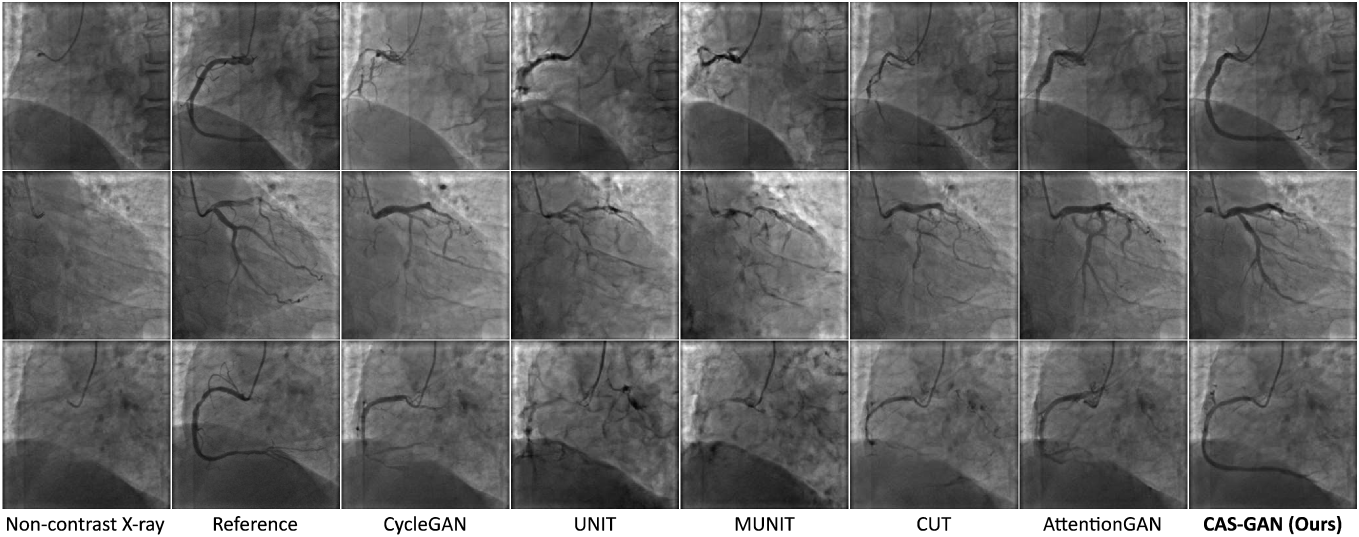

Fig. 3 showcases qualitative results generated by several baselines and our CAS-GAN. Reference images are real X-ray angiographies obtained by injecting contrast agents111Since reference and non-contrast X-ray images are captured at different moments in the cardiac cycle, quantitative metrics are not applicable for measuring their similarities.. As seen, baselines frequently exhibit significant entanglement of backgrounds and vessels, leading to highly unrealistic outputs. This issue is particularly evident in the first and third rows of Figure 3, where there is a total loss of structural consistency in vessels. Moreover, baselines fail to infer vessel bifurcations based on background prior. For example, in the second row of Figure 3, all baseline models cannot generate a crucial bifurcation at the position indicated by the catheter. In contrast, CAS-GAN can effectively disentangle and understand the complex interrelationships between backgrounds and vessels. This capability allows it to maintain structural integrity and precisely generate vessel bifurcations, markedly outperforming the baselines.